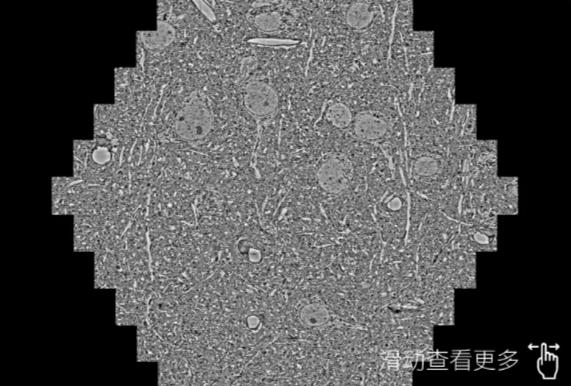

鼠脑切片。左图使用白沙蔡司白沙扫描电镜MultiSEM706对165μmx143pm面积区域成像,耗时仅需1.5秒。右图为鼠脑切片中30μm区域放大效果。样品由芝加哥大学B.Kasthuri提供。